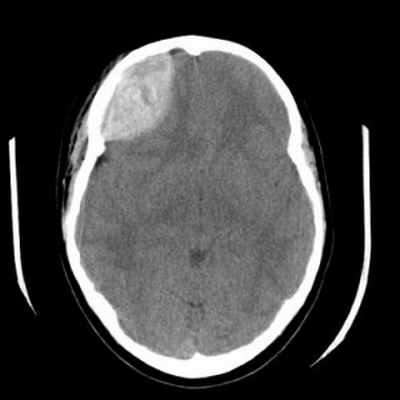

Эпидуральная гематома (экстрадуральная гематома) имеет травматическое происхождение. Это скопление крови внутренний костной пластинкой и твердой мозговой оболочкой. Обычно гематома расположена под областью перелома костей черепа. Причиной кровоизлияния является разрыв оболоченной артерии. Встречаются эпидуральные гематомы вдвое реже субдуральных. По форме гематома двояковыпуклая. Чаще всего диагностируется в неотложных условиях методом КТ. МРТ обычно применяется при спинальных эпидуральных гематомах.

КТ. Эпидуральная гематома.

Если рассмотреть эпидуральную гематому на полученных томографических снимках, то можно отметить ее особенную форму. Она напоминает двояковыпуклую линзу, что соприкасается с костью. Иногда при переломе черепа можно наблюдать такую картину: перелом кости находится прямо в области дна гематомы.

Абсолютно точный признак эпидуральной гематомы – это наличие у углов скопления крови, так называемых, ликворных «стрелок», которые появляются в случае разрыва арахноидальной оболочки. При этом ликвор постепенно переходит из арахноидальной полости в субдуральное пространство. Тут же можно наблюдать присутствие костных отломков. Что касается строения эпидуральных гематом, то их структура по обыкновению однородная. При травмах очень редко можно встретить неоднородное скопление крови или наличие газа в черепе.